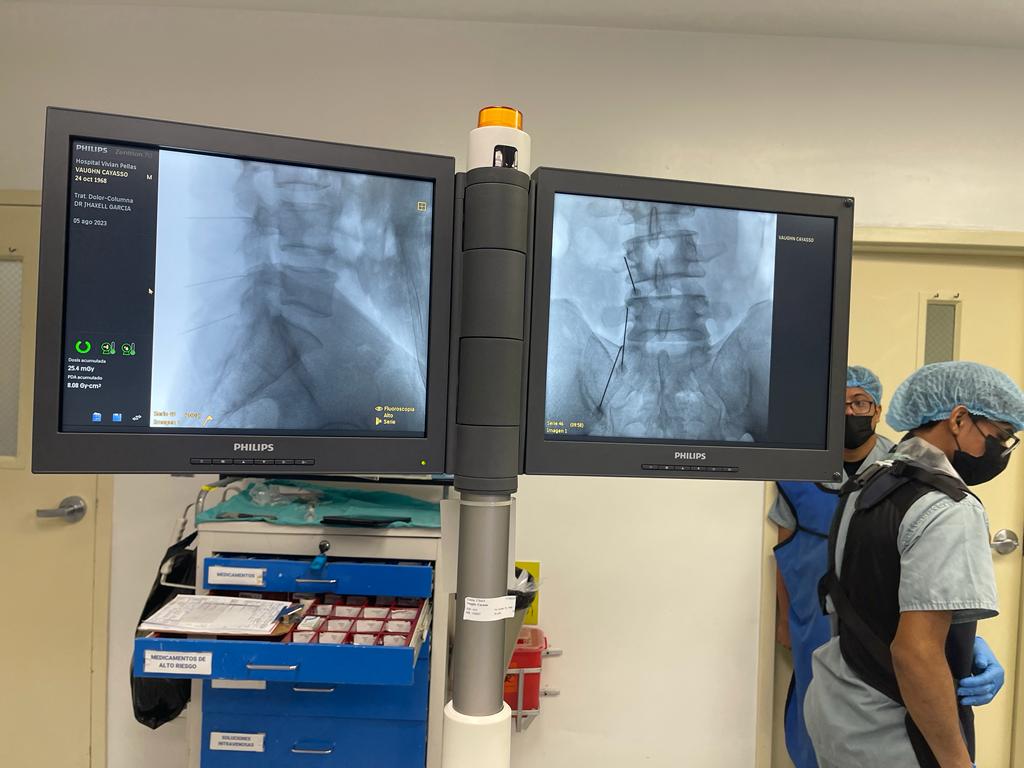

3. Rizólisis (Ablación por radiofrecuencia)

Procedimiento no invasivo que utiliza radiofrecuencia para desactivar nervios que transmiten dolor crónico en la columna.

Rizólisis (Ablación por Radiofrecuencia)

Técnica mínimamente invasiva para tratar el dolor crónico articular de la columna

La rizólisis es un procedimiento no quirúrgico que utiliza energía de radiofrecuencia para inactivar de forma selectiva los nervios responsables de transmitir dolor desde las articulaciones facetarias de la columna.

¿Para quién está indicada?

- Pacientes con dolor lumbar o cervical crónico, de origen mecánico

- Artrosis o degeneración de las articulaciones facetarias

- Dolor que no responde a tratamiento conservador (analgésicos, fisioterapia, bloqueos)

- Personas que no son candidatas a cirugía mayor

Beneficios

- Procedimiento ambulatorio

- Bajo riesgo de complicaciones

- Mejora del dolor durante meses (en ocasiones más de un año)

- Puede repetirse si reaparecen los síntomas